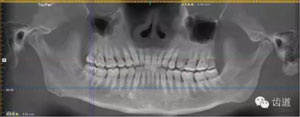

術(shù)前放射片

放射檢查:11,21根中三分之一至根尖三分之一處折斷。